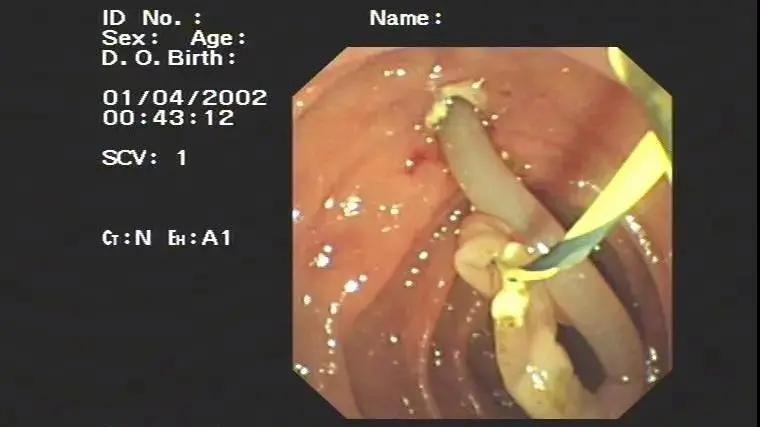

接诊的医生首先考虑到了存在胆道蛔虫的情况,但儿童家属表示没有发现过有类似情况,经过完善磁共振检查,发现胆管的下段存在一团可疑的条索团块,经过保守治疗,患儿每天都有数次剧烈的腹痛,家长经过慎重考虑,同意了肝胆外科医师的进行内镜ERCP治疗的意见。

经过1个小时左右的内镜手术操作,从胆总管内拖出了一团软绵绵的死亡虫体,而这就是引起腹痛的罪魁祸首。